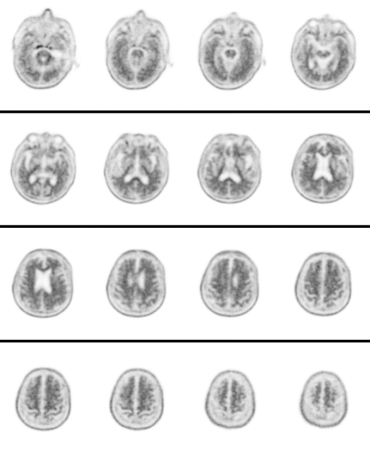

Aβ(18F-AV45)PET脑成像,通过正电子核素标记的示踪剂实现脑内Aβ沉积的活体可视化,在分子水平无创定位、高准确度地评估阿尔茨海默病患者脑内Aβ蛋白沉积情况。案例:男,74岁。

主诉:近期记忆力差2年,逐渐加重。

检查目的:临床诊断阿尔兹海默症,现进一步检查。